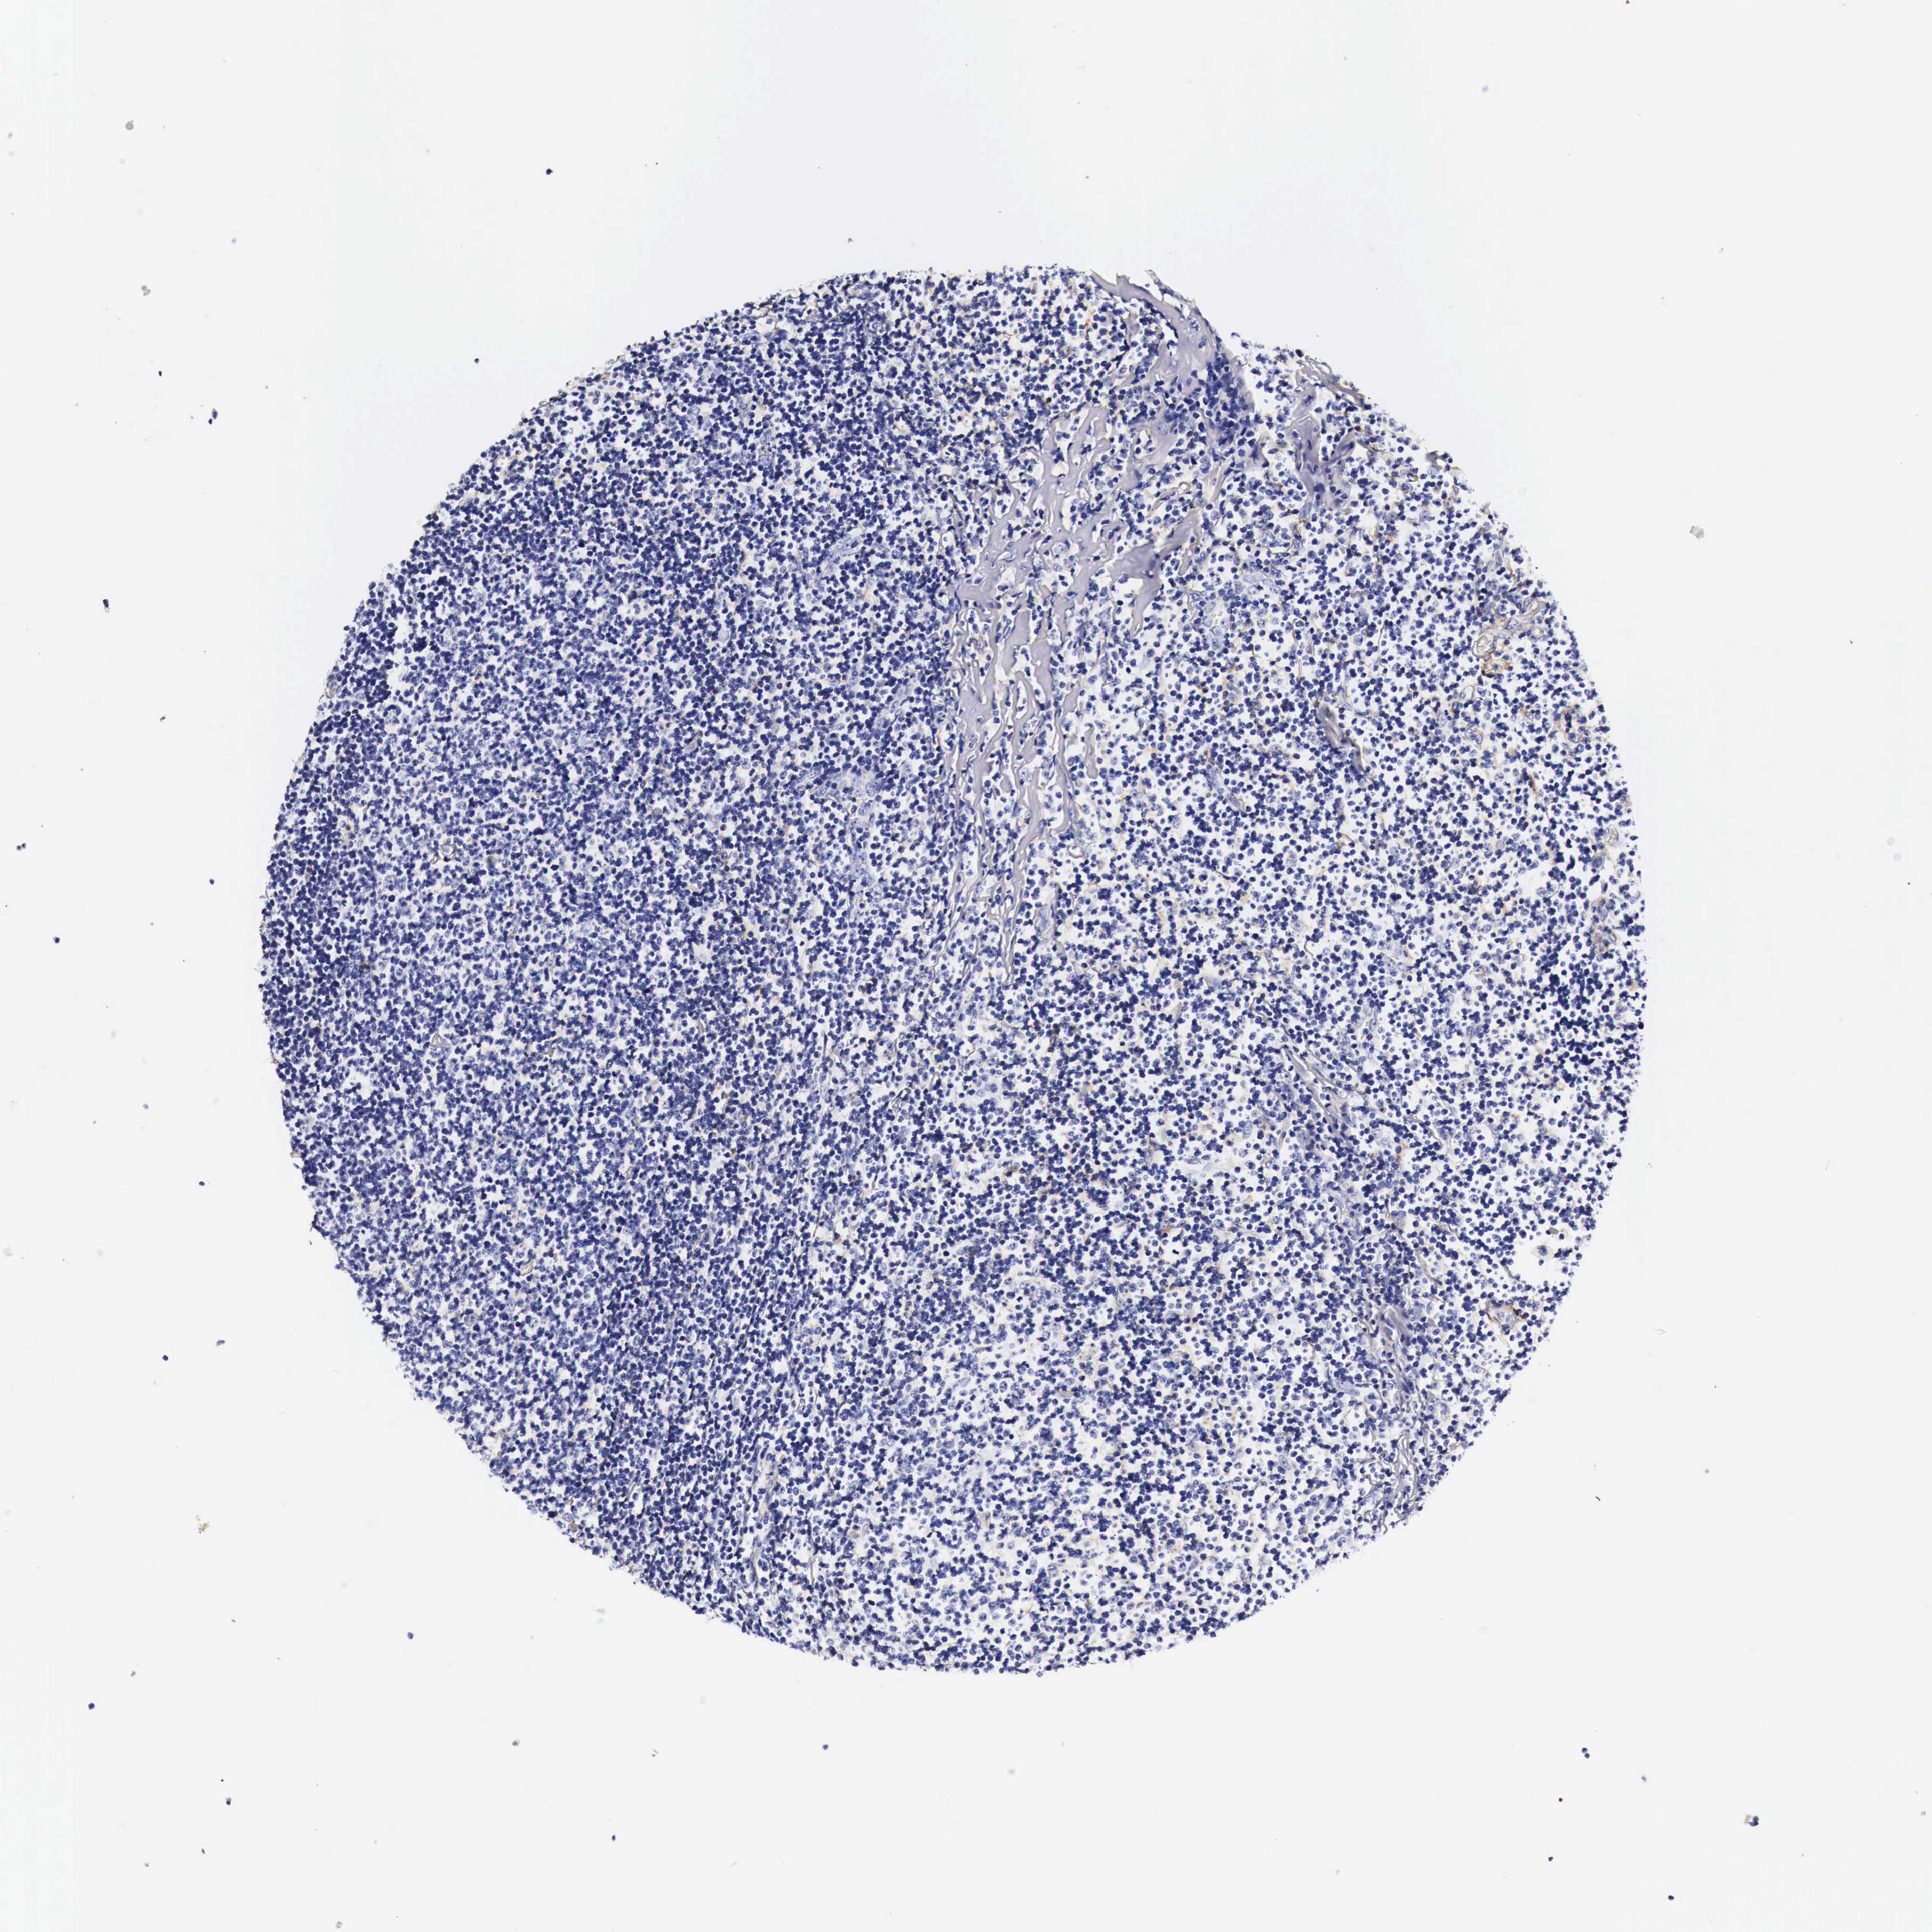

CANCER LYMPHOMA Show tissue menu

LYMPHOMA - Protein expressioni

A mouse-over function shows sample information and annotation data. Click on an image to view it in a full screen mode. Samples can be filtered based on level of antibody staining by selecting one or several of the following categories: high, medium, low and not detected. The assay and annotation is described here.

Each image is clickable and will lead to virtual microscopy that enables deeper exploration of all samples and also displays staining intensity scores, fraction scores and subcellular localization as well as patient and tissue information for each sample.

Malignant lymphoma, non-Hodgkin's type, High grade

Hodgkin's disease, NOS

Malignant lymphoma, non-Hodgkin's type, Low grade